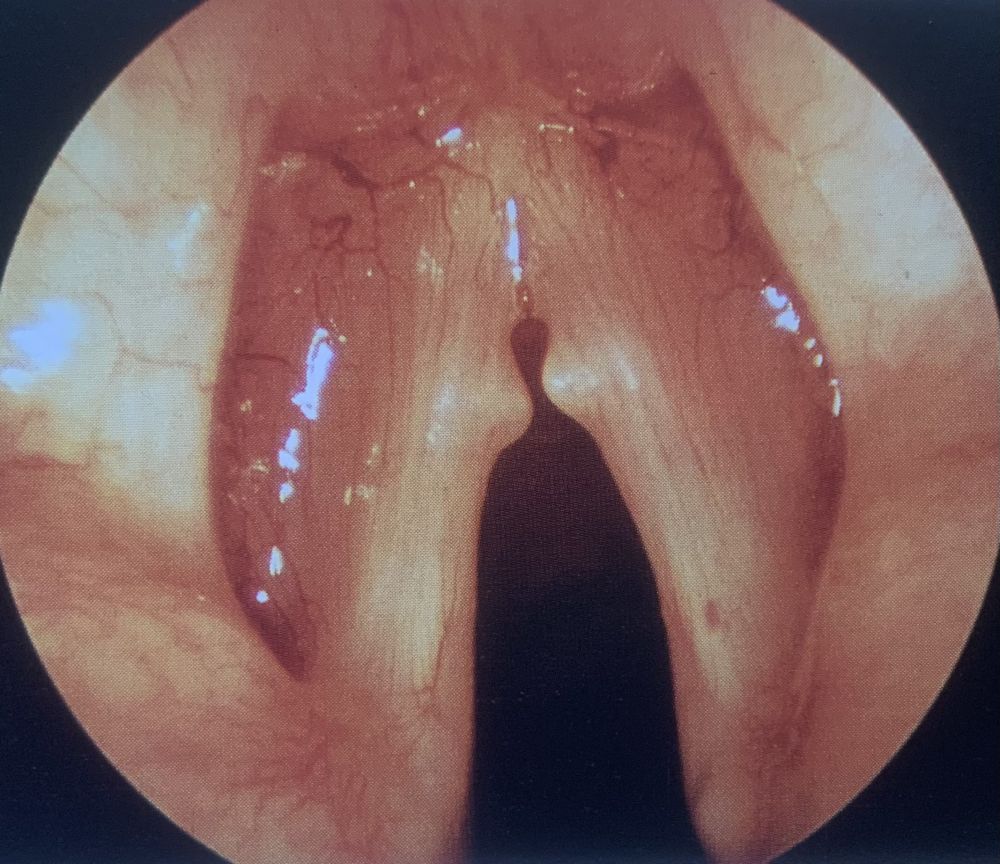

Noduli delle corde vocali